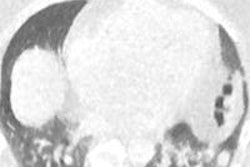

Computer-aided detection (CAD) technology was found to be invaluable for detecting and treating craniosynostosis, or premature fusion of skull sutures in infants. But CAD turned in mixed results in breast MRI, with improved sensitivity but no significant upgrade in overall accuracy.